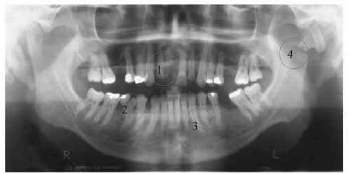

Tendo como referência a imagem radiográfica acima, assinale a opção que apresenta a identificação incorreta.

Com relação aos dentes mostrados na radiografia apresentada no texto, assinale a opção correta.

I Pode ser indicado no dente 26 a colocação de núcleo radicular e de uma coroa total estética, se o tratamento endodôntico estiver adequado.

II Houve perda de espaço mesiodistal que precisa ser recuperado antes da colocação da restauração definitiva.

III O material estético mais indicado é o cerômero.

IV Houve perda de estrutura na distal do dente 15, provavelmente por iatrogenia durante preparo cavitário anterior.

A quantidade de itens certos é igual a